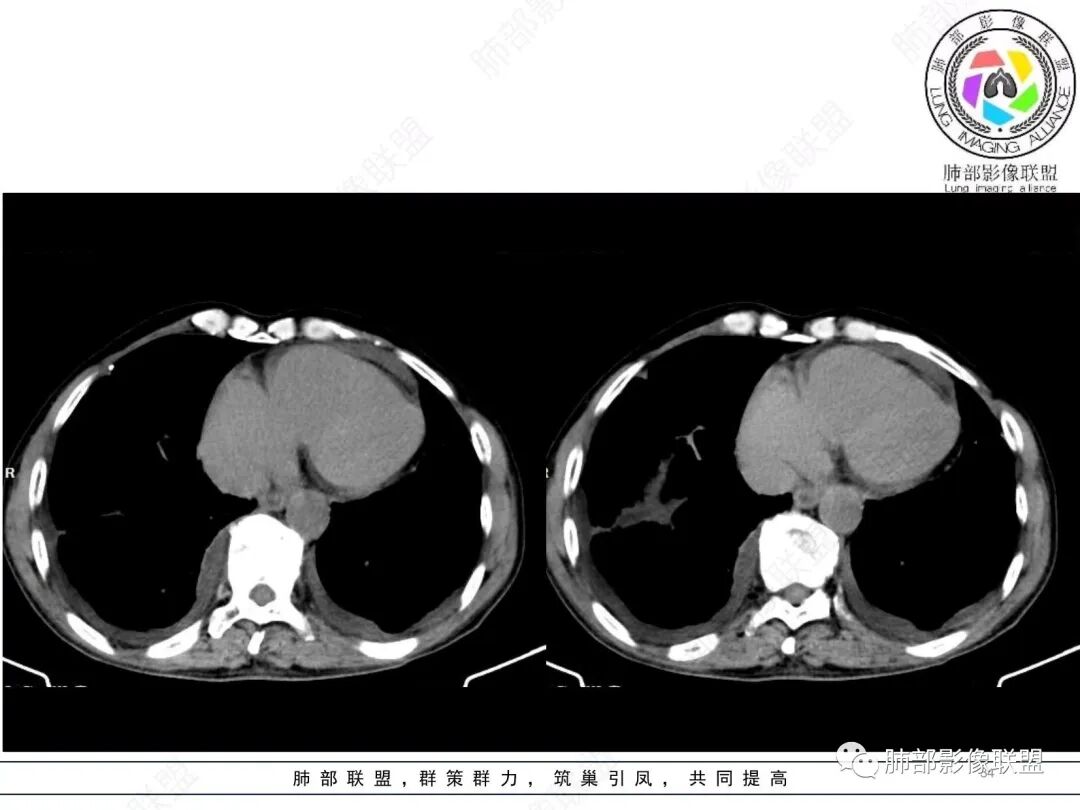

嘻嘻:2022.1.11号肺窗及增强

左房这么厉害,这个结果不对啊

肺动脉是栓塞吗?

不吝慷慨:

还是肺动脉慢性栓塞

有栓塞,但是需要排除肿瘤引起的栓塞和瘘形成

栓塞也是左房

左房是因为回流血量少而引起的密度不均匀吧

南边:

有道理。对,应该朝这方面考虑。

我觉得左肺动脉可能还是有炎性病变

还是慢性肺栓

6.心脏影增大,右房室增大为主。(增强:左心房及肺静脉入口见充盈缺损)

(增强:左肺动脉充盈缺损、闭塞)

2.影像右侧肺水肿提示左心回流障碍。左心房及肺静脉入口见充盈缺损提示血栓存在。

5.影像左肺动脉栓塞、闭塞——上下肺动脉以远相对纤细——左肺动脉“断供”,且存在支气管动脉扩张可能。